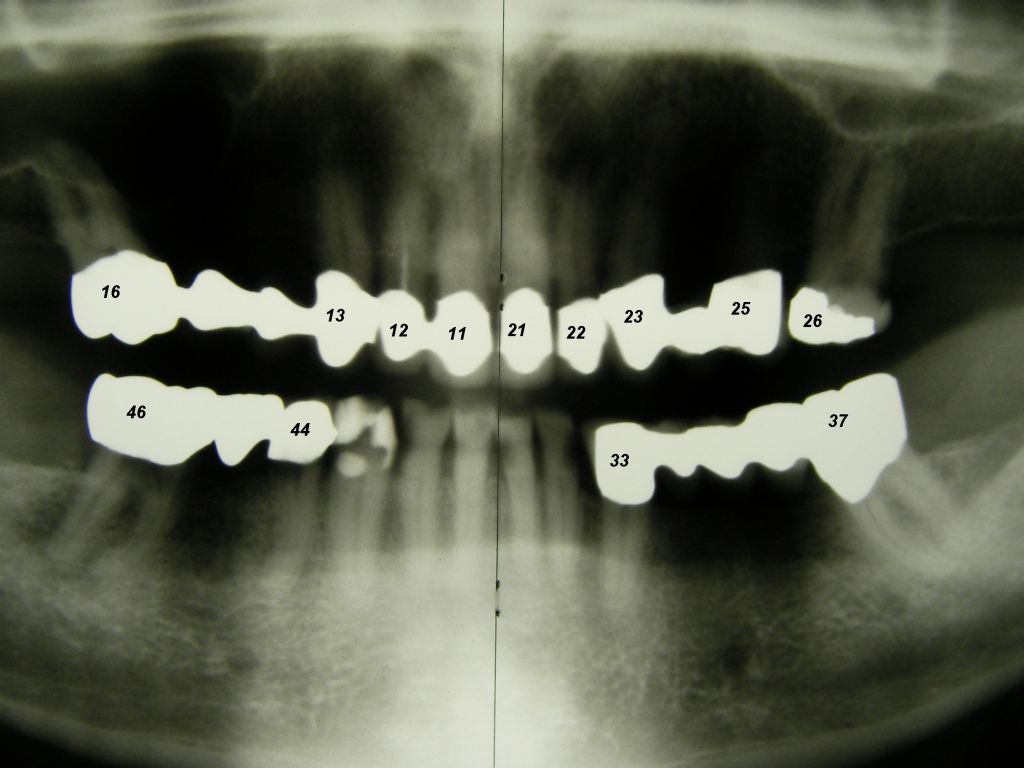

Das etwas dunkle Röntgenbild links(6/2003) zeigt diverse Probleme. Hier interessiert, daß der Zahn 22 (sprich: "zwei", "zwei") am 28.10.05 Schmerzen bereitete, weil der Zahnnerv unter Eiterbildung abgestorben war. Es brauchte 3 medikamentöse Einlagen, bis der Zahn ruhig war und am 18.11.05 eine Wurzelfüllung und einen Titanstift in den Wurzelkanal bekommen konnte. Bei der anschließenden Röntgenkontrolle rechts fiel der schlechte Randschluß der Krone 22 auf. |

Weil auch die anderen Schneidezahnkronen (12-22) durch Randreparaturen und den schlechten Randschluß erneuerungsbedürftig aussahen, wurden 4 Einzelkronen geplant. Vorher hieß es aber noch, die schlechte Wurzelfüllung im Zahn 12 (Röntgenbild links) besser zu machen. Hierfür wurden am 17.2.06 die alten Kronen 11 und 12 entfernt. Rechts das Bild nach Entfernung von alten Füllungen und Karies. | |

Eine Vollkeramikkrone (Keramik ohne Metallunterbau) ist demgegenüber bruchanfälliger. Der Vorteil der Vollkeramikkrone ist allerdings, daß bei Rückgang des Zahnfleisches auch nach vielen Jahren kein dunkler Metallrand sichtbar werden kann. Allerdings kann man diesen Metallrand auch sehr schmal gestalten, wie das folgende Beispiel zeigt. Wegen der starken Zerstörungen mußte der Kronenrand tief unter das Zahnfleisch gelegt werden. Das ist einerseits ungünstig, weil es Zahnfleischentzündungen fördern kann (die hier aber nicht zu sehen sind), andererseits günstig, weil nicht zu befürchten ist, daß das Zahnfleisch so weit zurückgehen wird, daß man den Kronenrand sehen wird. Wenn man nicht so weit unter das Zahnfleisch mit dem Kronenrand gehen muß und mehr Platz hat, kann man auch einen keramischen Rand (eine "keramische Stufe") wählen. Das erhöht die Laborkosten, aber man hat die Sicherheit, daß es langfristig keinen sichtbaren Metallrand geben kann. Auch eine Vollkeramikkrone ist natürlich möglich. Oft ist nach vielen Jahren aber gar nicht die Krone das Problem, sondern die dunkle Zahnwurzel, die vom Zahnfleisch entblößt wird. Wie man unten sieht, sind insbesondere wurzelbehandelte Zähne sehr dunkel. Hier hilft dann doch nur wieder, mit dem Kronenrand tief unter das Zahnfleisch zu gehen, um die dunkle Wurzel abzudecken. Patient, 67 Jahre. Die Bilder sind alle zur Vergrößerung anklickbar! |